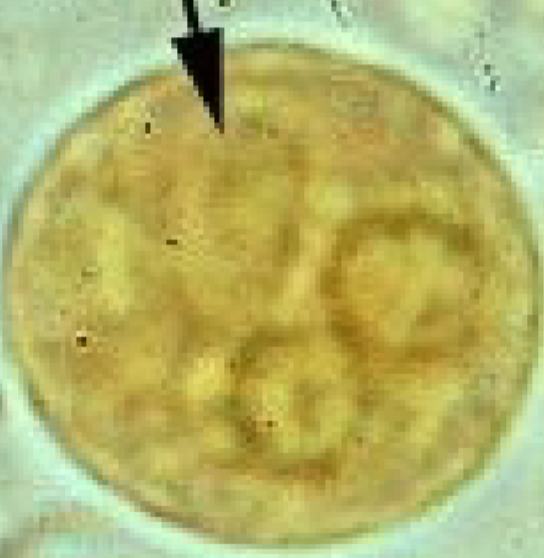

Entamoeba histolytica (cyst) >10

Entamoeba histolytica (cyst)

Entamoeba histolytica (cyst)